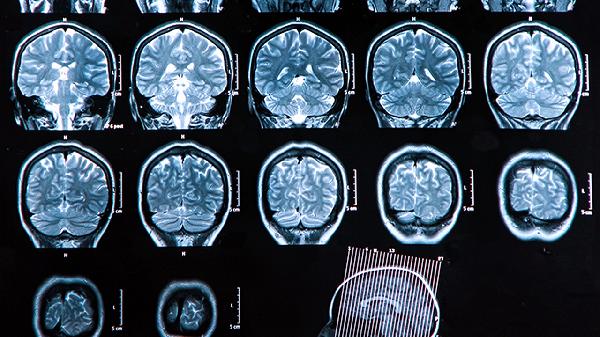

脑淤血康复期需严格控制血压血糖,每日钠摄入应低于5克,保持2000毫升左右饮水量。卧床患者每2小时需翻身预防压疮,肢体康复训练应在专业医师指导下循序渐进开展。定期复查头颅CT监测血肿吸收情况,出现头痛加剧、意识改变等预警症状须立即返院诊治。心理疏导与营养支持对长期预后至关重要,家属应参与全程照护计划制定。